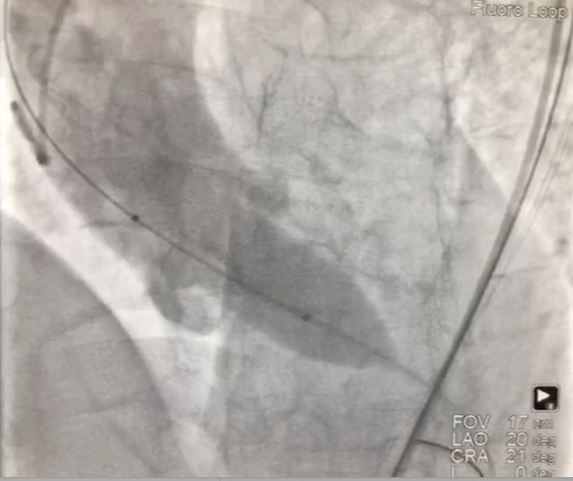

经左股动脉入路,顺利跨瓣后,选取20 mm球囊于180 bpm下快速起搏预扩,显示无漏,左、右冠脉未受影响,但可见左冠窦、无冠窦巨大钙化团块。

图片